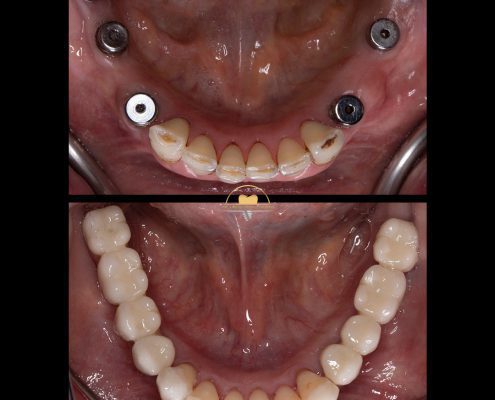

دکتر عباس گشاده رو متخصص ایمپلنت

دکتر عباس گشاده رو متخصص ایمپلنت در تهرانتلفن: 02126706197